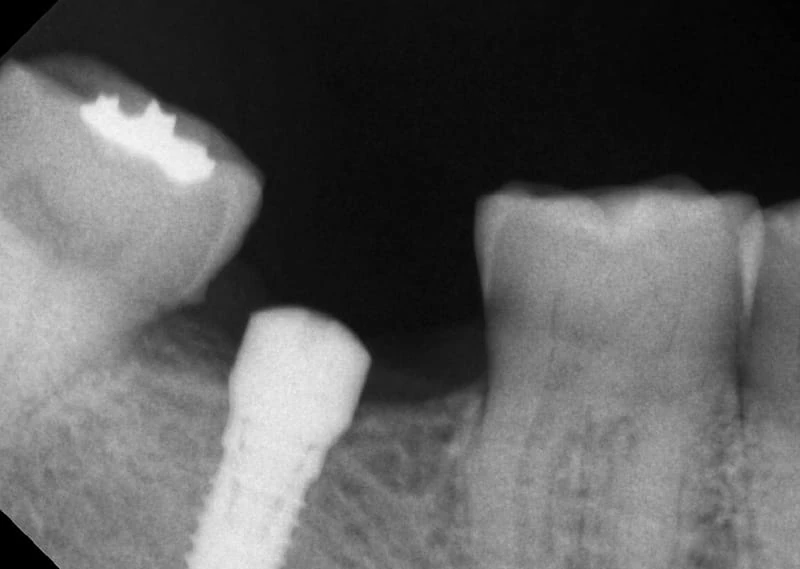

- 入人工牙根(進行植牙第一階段及第二階段)。<圖二~圖五>

第二階段完成X光片 <圖五>